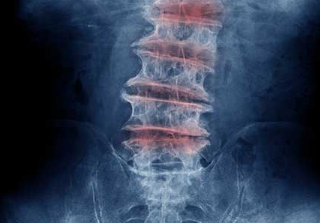

요추 관절염 원인과 증상, 치료방법 : Lumbar arthritis 18

요추 관절염 원인과 증상, 치료방법 : Lumbar arthritis

척추 관절의 염증 요추 관절염은 척추에 영향을 미치는 관절염의 증상입니다. 가장 흔한 요추 관절염 원인은 골관절염입니다. 척추 관절염으로도 알려져 있으며, 이는 요추의 가장 낮게 위치한 척추 관절에서 골관절염 (OA, osteoarthritis)...